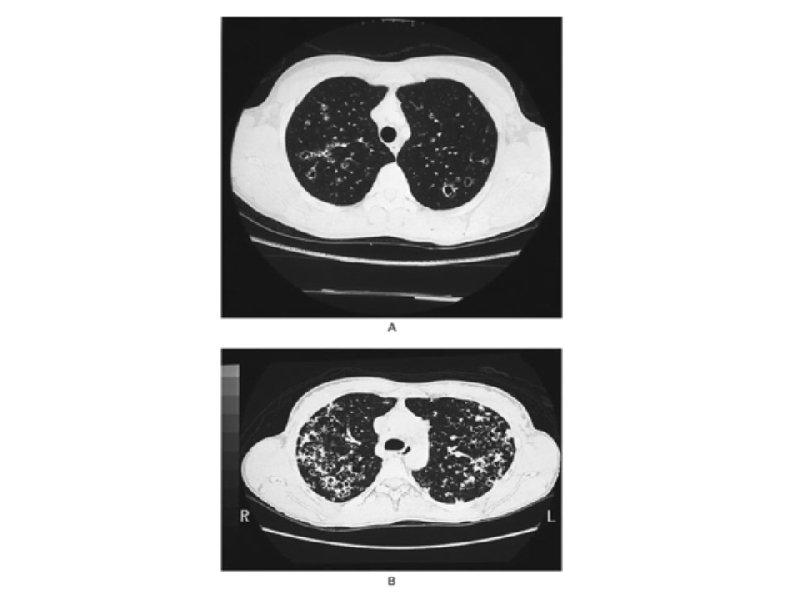

Chest Radiography a. Symmetrical micronodular and Interstitial infiltration predominantly in the middle and upper lobes b. Increased lung volumes c. Rare: alveolar infiltrates, hilar LAD, pleural effusion

Histopathological Features a. Proliferation of Lagerhans Cells along the small airways serves as the nidus of cellular/fibrotic nodules from 5 mm to 1. 5 in size. Eosinophils may be present b. In severe disease, nodules may interconnect and cavitate to produce distinctive honeycomb-like structures c. Given that most patients are smokers, concominant COPD and ILD 2/2 respiratory bronchiolitis is often present

Interval History a. Repeat CT imaging showed resolution of effusions, but persistent nodules, concerning for metastatic disease of unknown primary b. PET Scan and Abdominal CT scans did not show evidence of extrapulmonary malignancy c. The patient returned two months later for a thorascopy with lung wedge resection of a characteristic nodule